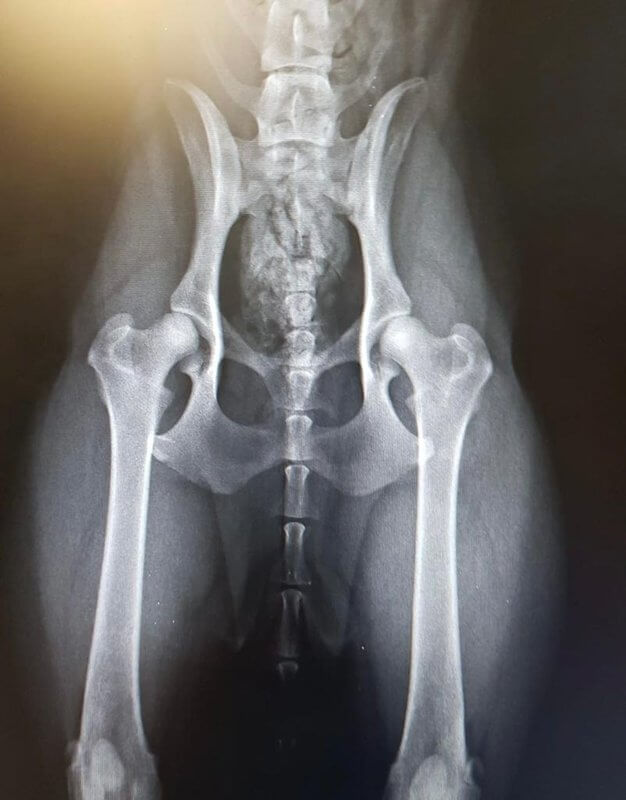

PS das Bild wurde vom Tierarzt abfotografiert

Es gibt ja mit Sicherheit einige unter euch, die mehr Ahnung zur Auswertung des HD-ED röntgen haben als ich.

Feli wurde von einem sv Tierarzt geröngt mit einem Ergebnis, " im schlimmsten Fall, noch zugelassen "

Heute kam das vom sv ausgewertete mit dem Ergebnis mittelgradige HD, zuchtausschluss.

Ich bin sehr überfordert, weil feli auch keinerlei Anzeichen einer D Hüfte hat.